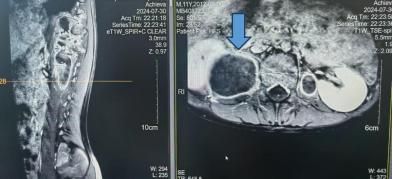

直到今年7月初,成成偶尔觉得腰痛。家里人带他到浙大儿院检查后,被发现脊髓受压、腰大肌巨大脓肿,而造成这一切的罪魁祸首是骨结核。

随后,浙大儿院感染科、浙江省儿童结核病艾滋病临床诊治中心针对成成的情况,完善了进一步的检查,为孩子制定了合适的诊疗方案。

怎么还会有骨结核?感染科结核病专科门诊医生李嫣表示,对于结核病来说,除了肺结核之外,还有结核性胸膜炎、结核性脑膜炎、纵膈淋巴结核、肺门淋巴结结核、骨结核等各种全身结核感染的情况。对于一些结核潜伏时间较长的患儿来说,身上很可能出现多种结核感染的严重情况。因此,及时筛查出这些患儿非常重要。